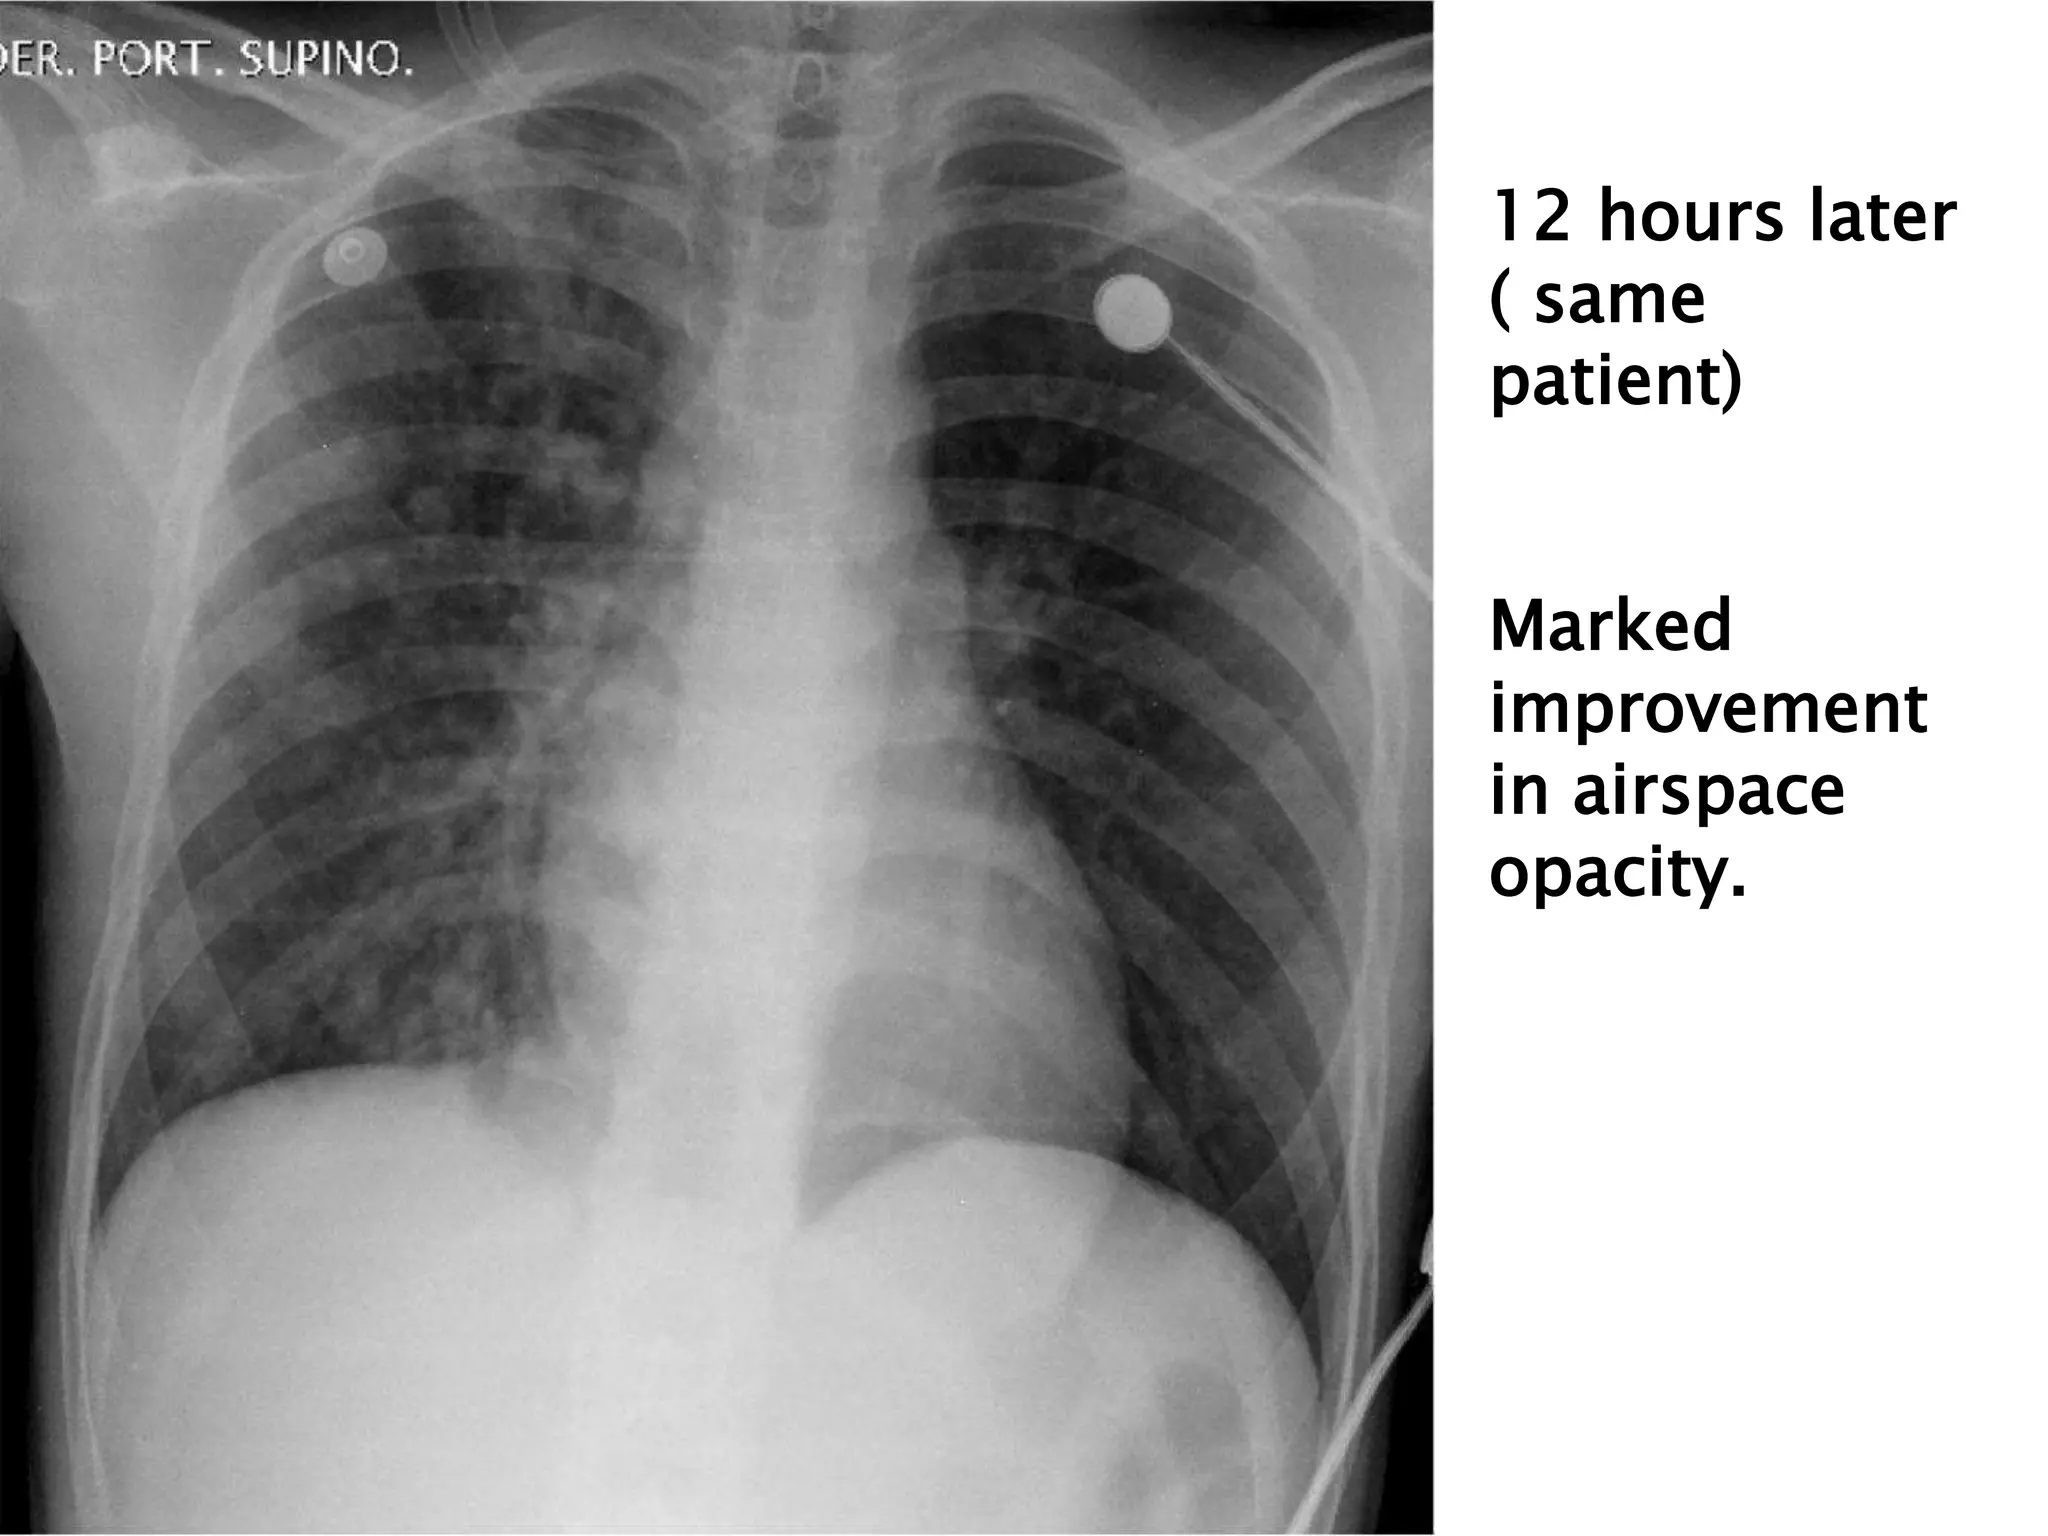

Patient admitted with progressive respiratory distress 24 hoursafter arriving at town at 2700 meters above sea level. Right greater than left indistinct airspace opacity

12 hours later (same patient) Marked improvement in airspace opacity.